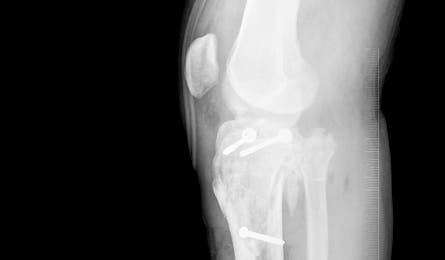

Side x-ray of Harris’ leg

Injuries Spiral tibia fracture and compartment syndrome

Justin Harris and his younger brother Jeremy were prepared for the 80-foot rappels and chest-high pools they’d encounter on the seven-hour descent of Chute Canyon in Utah’s San Rafael Swell. But when the Parowan, Utah, resident slipped on a straightforward 12-foot drop and shattered his left leg below the knee, everything changed. “I didn’t know if I’d ever get out of that canyon,” he says, recalling the 2003 incident.

Temperatures plunged to 9°F overnight as Jeremy hiked alone to summon help, a five-hour trip that took more than 22 because he missed a turn. Rescuers didn’t reach Harris until a day and a half after the accident. By that time, his kidneys were shutting down, and swelling in his leg had cut off circulation to his foot. “I was mentally prepared for another day [in the canyon], but things with my body were serious. I wasn’t sure I’d live until I heard the rescuers’ voices,” recalls Harris.

Six weeks later, he and his doctors decided to amputate. His left tibia had broken in so many places that he couldn’t overcome the swelling and infection. After a long, uncertain, and painful wait, “it was a relief to let my leg go and start healing,” says Harris. Seven months after surgery, he returned to coaching his son’s football team atop a $22,000 titanium and carbon fiber prosthetic. He has since skied, hiked, and even scrambled to the top of Zion’s Angels Landing. “I have a greater respect for the outdoors,” he says. “I’ve scaled back on the extremes, but my injury has challenged me to do more and stay strong.”